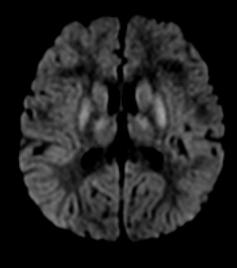

腦挫傷 - DAI

腦挫傷 - Hypoxic Encephalopathy